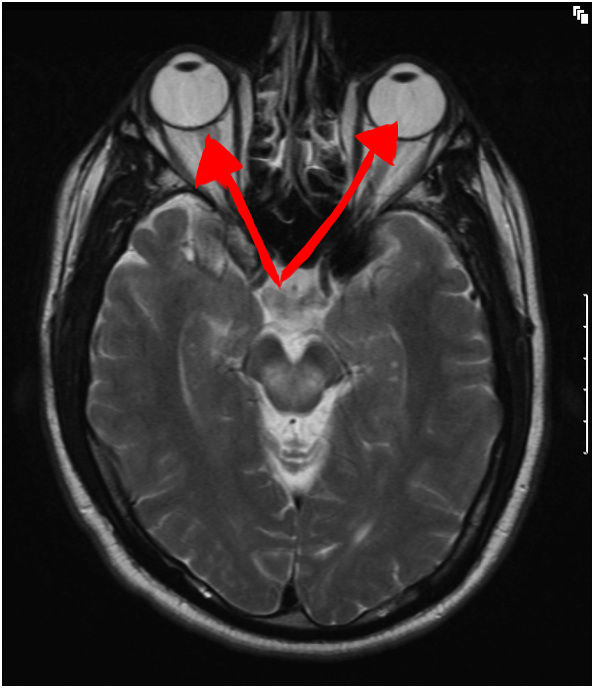

Once you’ve completed the neurology exam, you order a head MRI, because apparently every person gets a head MRI if they have ever fallen down before. Your intrepid student doctor will then interpret that MRI by saying, “I am pretty sure these are your eyeballs.”

Seriously, how creepy are MRI’s? (Also, if you care, this is a T2-weighted axial MRI displaying mild hyperintensities in bilateral thalamic regions, which is apparnetly characteristic for Wilson’s disease, which is on House like all the time. I just picked it because it had GREAT terrifying eyeballs.)